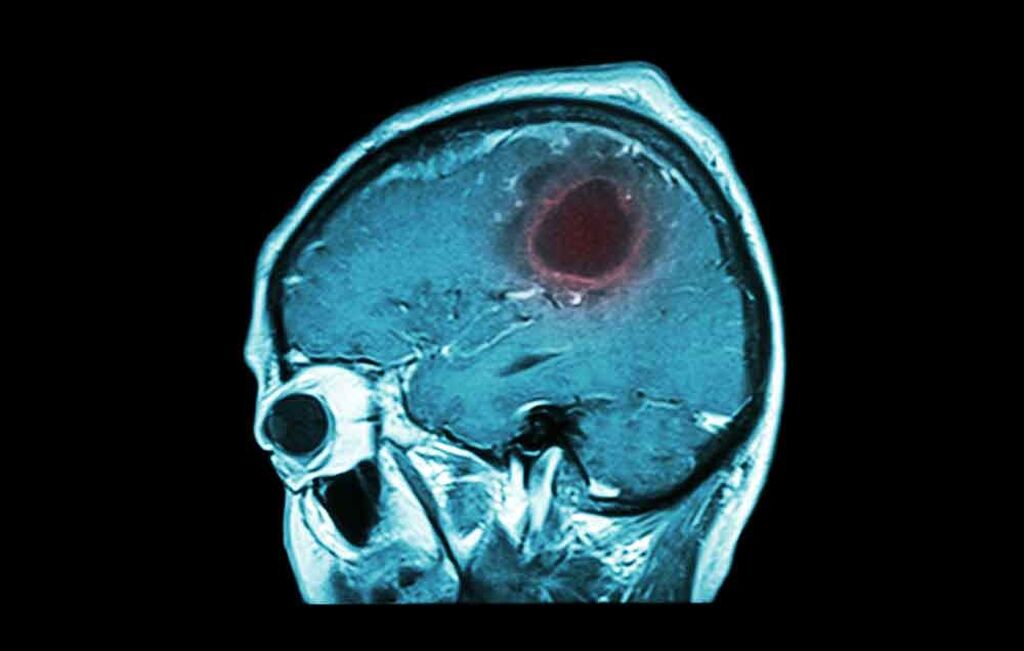

Όγκος στον εγκέφαλο

Ο πονοκέφαλος στην αρχή είναι ελαφρύς και «πηγαινοέρχεται». Με την πάροδο των ημερών δυναμώνει σταθερά και είναι χειρότερος τις πρωινές ώρες. Ταυτόχρονα υπάρχει ζάλη, έλλειψη συγκέντρωσης και αλλαγές στη συμπεριφορά. Επιβάλλεται η επίσκεψη σε ειδικό.